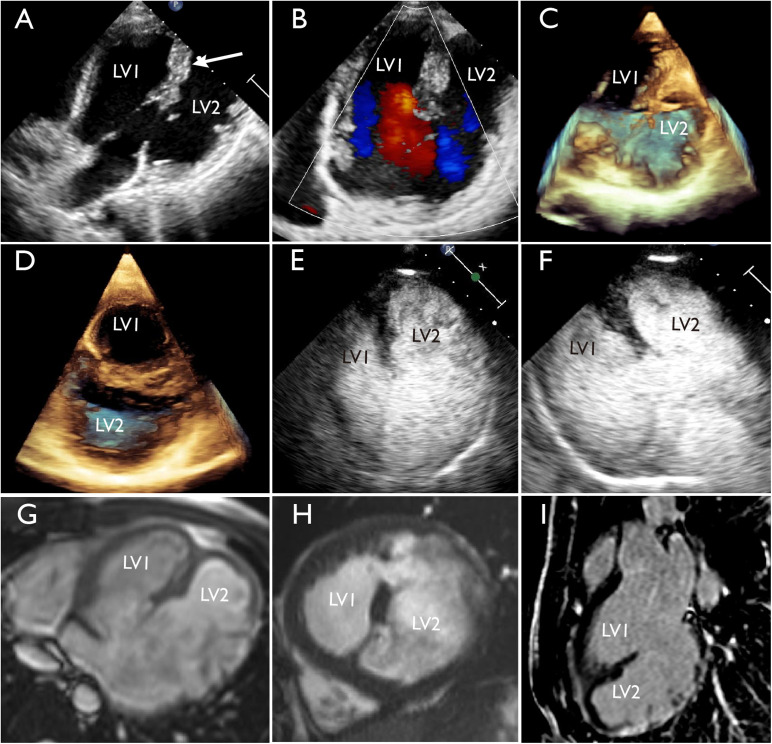

Visualization of Double-Chambered Left Ventricle by Multimodality Imaging.

双腔左心室的多模态成像。